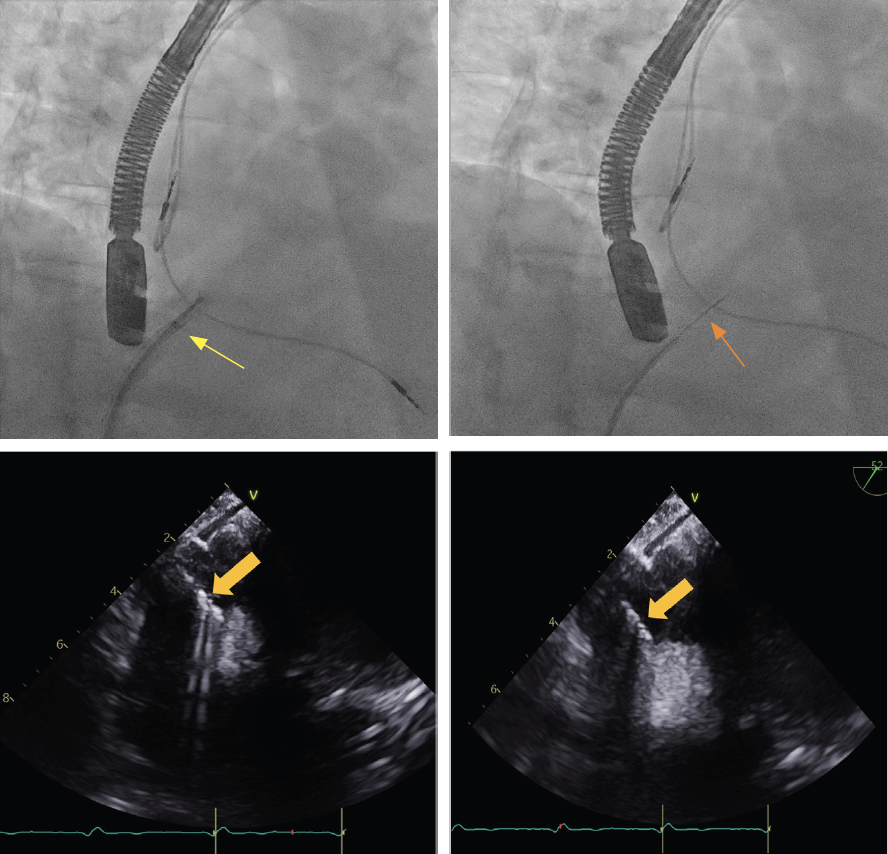

Transesophageal echocardiography at the time of the cardiac biopsy revealed a heterogeneous mass extending along the interatrial septum into the superior vena cava, which appeared partially occluded, as well as probable involvement of the aortic root. A Jawz endomyocardial biopsy forceps bioptome (EMB) (Argon Medical Devices) inserted through an 8.5-Fr Direx steerable sheath (Boston Scientific) was introduced into the RA (Figure 2). The bioptome was steered toward the RA mass at the inferior limbus of the fossa ovalis and several biopsies were obtained. However, the size of the samples was deemed to be insufficient for frozen section analysis. The EMB was then exchanged to a liver access Core needle (Cook Medical) through the steerable sheath and oriented toward the mass in the inferior limbus of the fossa ovalis where several biopsies were obtained. However, pathologic review of the core needle biopsy samples was inconclusive. Then, an endobronchial alligator forceps was used to biopsy the RA mass under intracardiac echocardiographic guidance, with no complications. Pathology was consistent with lymphoid tissue seen in lymphoma (Figure 3).